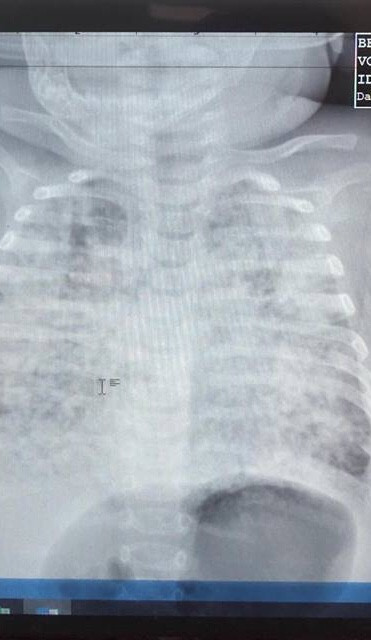

Bé trai 5 tháng tuổi phổi trắng xóa vì nhiễm lao từ cha ảnh 1Phim phổi bé trai tổn thương trắng xóa, lấm tấm do lao kê

Theo lời kể của chị N (28 tuổi, mẹ bé trai), sau khi chị hạ sinh bé thì phát hiện chồng mình bị lao phổi. Chồng điều trị được 2 tháng thì gia đình bé trai bắt đầu xuất hiện dấu hiệu sốt, ho liên tục 1 tuần, nhập viện địa phương uống thuốc không khỏi mà ngày càng khó thở hơn. Bé trai sau đó được chuyển đến BV Nhi đồng Thành Phố thì các BS cho biết phổi bé đã trắng xóa, kết quả xét nghiệm cho kết quả bé bị nhiễm lao kê nặng.